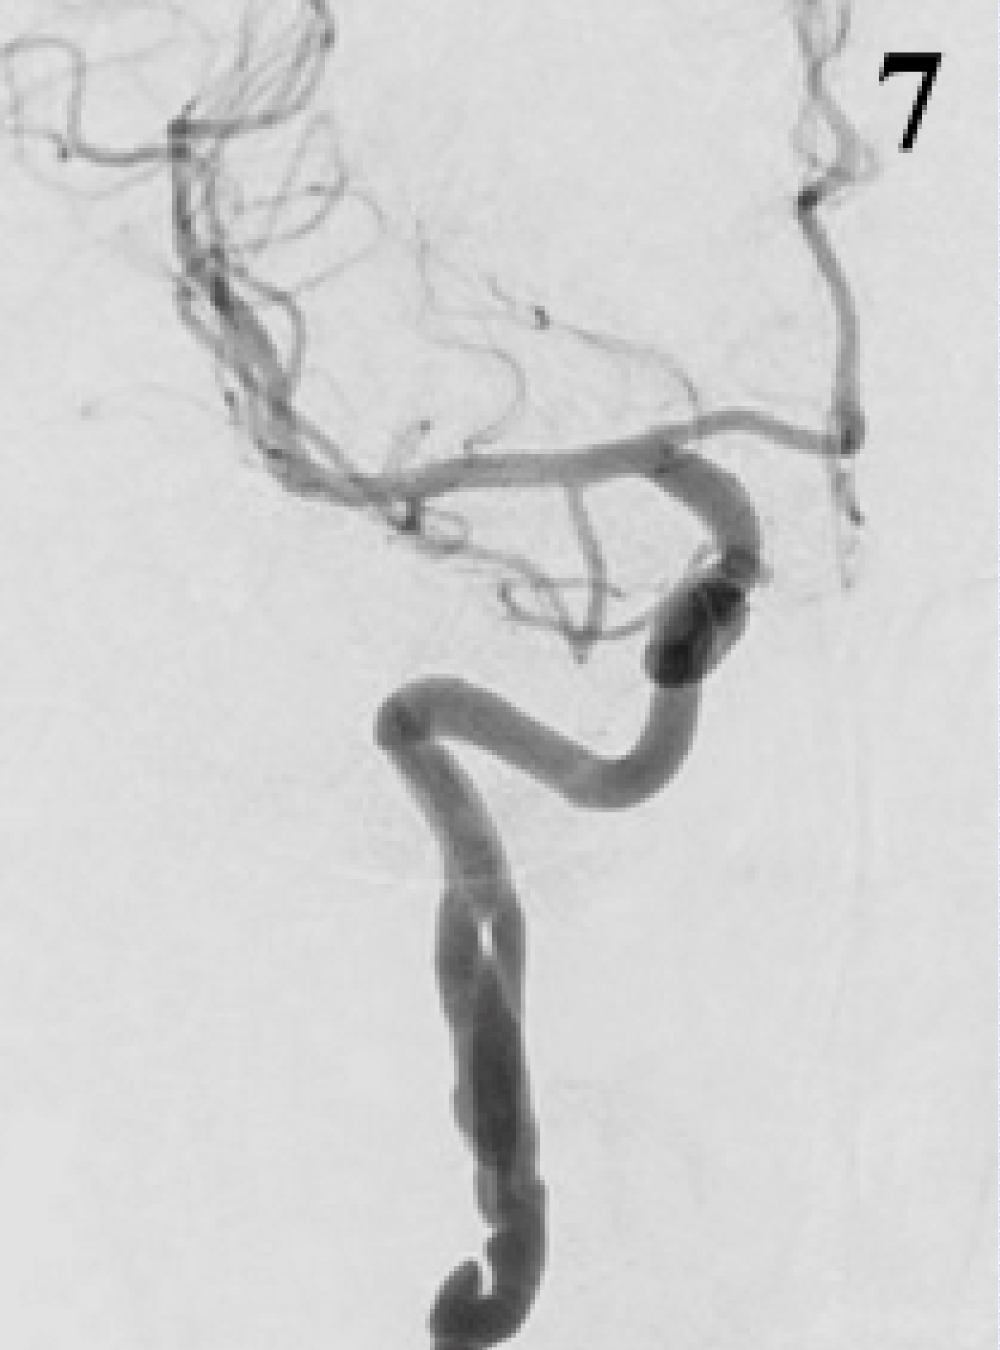

On 7th post-operative day the patient was symptoms free apart from a persistent headache. CT scan did not show re-bleeding or ischemic complications. On suspicion of vasospasm based on CTA, an angiography was performed revealing still injection of the aneurismal sac which also appeared increased in size (Figure 5). A shortening of distal end of stent, although still covering the aneurysm, was also noticed. An additional FD stent placement was discussed but a conservative management was eventually preferred, considering the positive clinical course. On 19th post-operative day a control angiogram showed complete exclusion of BBA without further changes of the stent (Figure 6). On 24th post-operative day the patient was discharged free of any neurological deficit (mRS 0). 3-months CTA followed by 6-months angiography (Figure 7) confirmed exclusion of the aneurysm and patency of the stent; the extracranial dissection was unchanged.

Figure 7: Control angiogram at 6 months, AP view: No more residual filling of aneurysm. View Figure 7